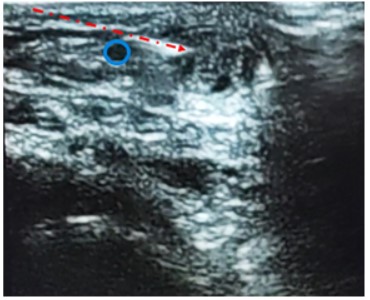

Figura 4. Ecografía corte transversal al tendón: En azul se visualiza la vena safena menor sin compresión (izquierda) y con compresión derecha (en amarillo se identifica el nervio sural.

Figura 6. Ecografía corte transversal al tendón: En azul se identifica la vena safena menor. La línea punteada roja representa la posición del reparo (aguja 50.8 en contacto con el tendón de Aquiles).